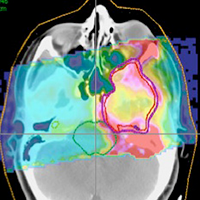

- From Medical Images to Genomics: A study of more than 300 cancer patients utilized information hidden within imaging tests to more accurately identify the radiation dose needed to kill a tumor.

- Data Mining for Improved Cancer Treatment: Medical physicists will present research on their use of data mining of more than 500 head and neck cancer cases to improve outcomes and decrease side effects.

Real-time insights designed to provide personalized approaches for head and neck cancer - Hidden Information Behind Imaging Tests For Cancer May Unlock New Approaches To Radiation Therapy

Radiomics: Medical Imaging Meets Genomics in the Fight Against Cancer

Characteristics of tumors that can remain hidden in medical images are being tested for the ability to predict risk, prognosis and response to cancer therapy. This approach is part of a powerful emerging field in medical physics called radiomics, which seeks to extract statistical information from images to make better treatment decisions. Radiomics research also helps determine how information from medical images can be combined with genomic information from individual patients to improve outcomes. A special session on Monday presents the fundamentals and latest advances in combining quantitative imaging and genomics in the practice of medical physics.

Characteristics of tumors that can remain hidden in medical images are being tested for the ability to predict risk, prognosis and response to cancer therapy. This approach is part of a powerful emerging field in medical physics called radiomics, which seeks to extract statistical information from images to make better treatment decisions. Radiomics research also helps determine how information from medical images can be combined with genomic information from individual patients to improve outcomes. A special session on Monday presents the fundamentals and latest advances in combining quantitative imaging and genomics in the practice of medical physics.